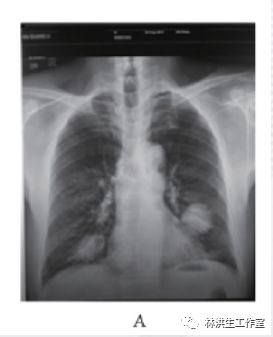

【现病史】2013年8月到中国人民解放军309医院就诊,查肺部CR片: 左肺上叶舌段占位( 3.1×3.8 cm2) ,右肺下叶占位( 1.3×2.4 cm2)( 见图 2) ,考虑恶性占位。行 CT 引导下肺穿刺活检病理( 病理号: 186488) :( 肺) 穿刺组织示弥漫增生的淋巴组织,细胞较为一致,结合免疫组化病变符合肺黏膜相关边缘区 B 细胞淋巴瘤( 见图1) 。患者因肿瘤较大,且伴顽固瘙痒,建议行化疗治疗,但患者因惧怕化疗不良反应而拒绝化疗。遂求诊于林洪生教授,寻求中药治疗。刻下症: 患者瘙痒剧烈,口服氯雷他啶、泼尼松等药抗过、外用倍氯米松止痒均无明显缓解,全身散在淡红色小丘疹,无疼痛,无咳嗽,无胸闷胸痛,因瘙痒无法入睡,二便正常,胃纳可。

A: 2013 年 8 月 23 日发病时,胸部 CR 片显示双侧肺肿物;